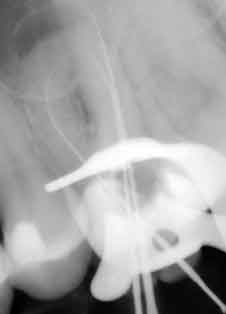

Zahnmedizinische röntgenologische Untersuchung (Bild 1):

Ø      Tiefe Füllung

Ø      Pulpakammer röntgenologisch nicht erkennbar

Ø      Verdacht auf sehr enge oder sogar obliterierte Wurzelkanäle

Ø      Starke Krümmung der mesialen Wurzel

Ø      Parodontitis apikalis erheblicher Größe, bzw. eine gut erkennbare periapikale Transluzenz im Bereich der MV-Wurzel

Bild 1